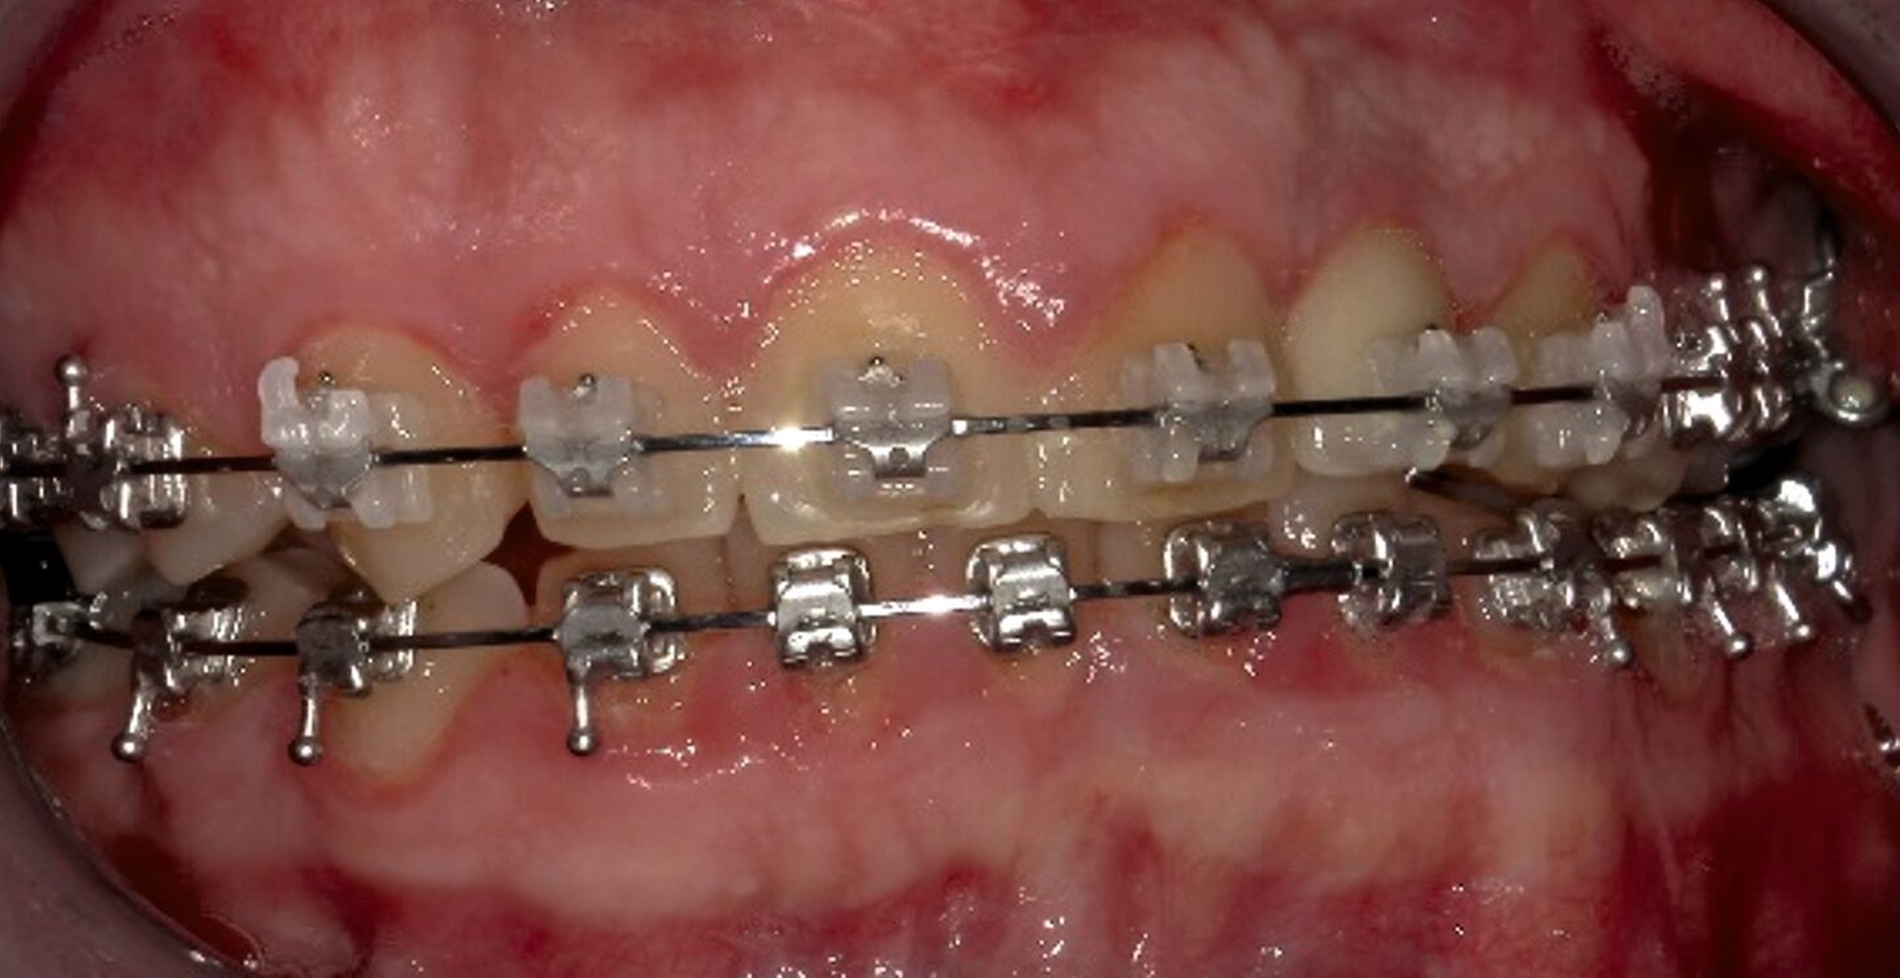

Nach diesem Eingriff schloss sich bis zum 17. Lebensjahr eine kieferorthopädische Therapie bei skelettaler maxillärer Retrognathie an. Der Zahn 22 war nicht angelegt, die Lücke wurde kieferorthopädisch offengehalten. Im Bereich 22 wurden nach Abschluss des Wachstums eine Augmentation durchgeführt und ein zahnärztliches Implantat inseriert. Dennoch konnten die Laterognathie des Oberkiefers mit einer Mittellinienverschiebung von 2,5 mm, der Tiefbiss sowie der Kreuzbiss auf der linken Seite nicht vollständig behoben werden (Abbildungen 1 und 2).

Gemeinsam mit den behandelnden Kieferorthopäden wurde aufgrund des abgeschlossenen Wachstums und der ausgeschöpften nicht-chirurgischen Maßnahmen die interdisziplinäre Indikation zur chirurgischen Korrektur der Dysgnathie gestellt. Anhand einer kephalometrischen Analyse trafen wir gemeinsam mit der Patientin die Entscheidung zur Durchführung einer bimaxillären Umstellungsosteotomie (Abbildung 3).